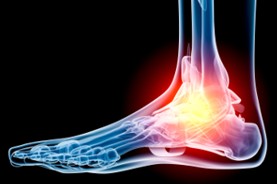

At the Red Deer Foot Institute, our Doctors are trained to specifically treat problems associated with your feet or ankles. Below are several of the most common problems that we see on a day to day basis: